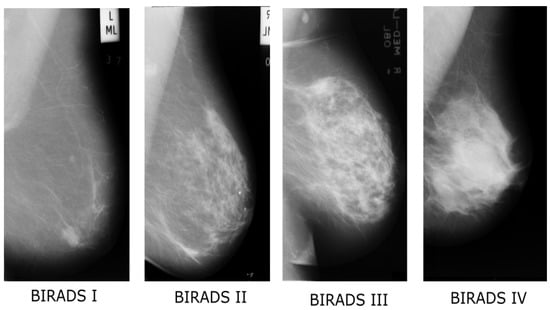

| BI-RADS | Breast Imaging-Reporting and Data System |